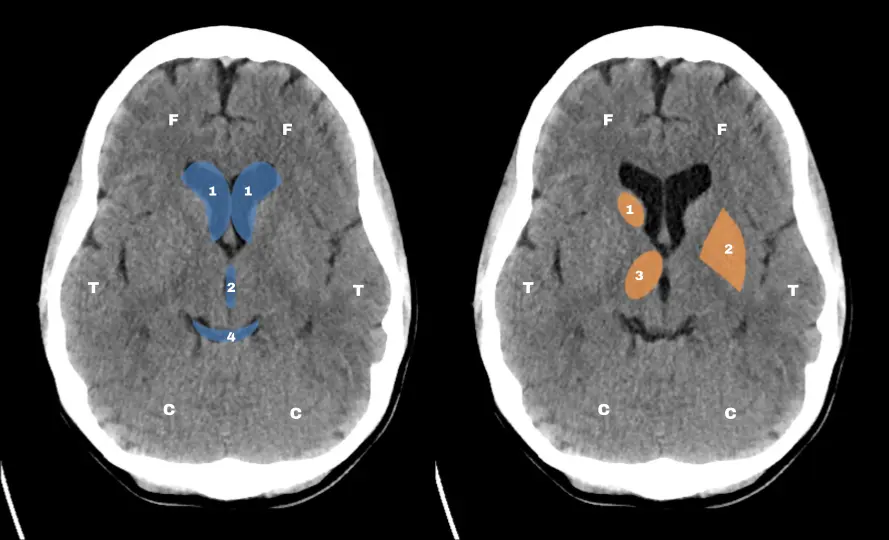

El doctor James Smirniotopoulos, neuroradiólogo y profesor universitario, propuso que bastaba con reconocer tres cortes axiales estratégicos para tener una idea global de la anatomía cerebral en la TC.

Los tres niveles clave son: el tronco encefálico, los ganglios basales y los ventrículos laterales. Una vez dominados, resulta mucho más sencillo interpretar variaciones y detectar alteraciones.

Estructuras clave en cada nivel

En el corte del tronco encefálico, es importante ubicar la cisterna supraselar (con su forma en estrella de  cinco puntas), el cuarto ventrículo y las prolongaciones temporales de los ventrículos laterales.

En el nivel de los ganglios basales, se identifican los cuernos frontales de los ventrículos laterales, el tercer ventrículo, la cisterna cuadrigémina (con apariencia de “sonrisa”) y los núcleos profundos, caudado, lenticular y tálamo óptico

Por último, en el corte de los ventrículos laterales, conviene reconocer el septum pellucidum, la línea media y el cuerpo del núcleo caudado.

Estos elementos son puntos de referencia para evaluar tanto la anatomía normal como desplazamientos o efectos de masa.